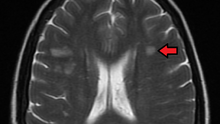

Чем опасен рассеянный склероз и причины его возникновения.

Все действия, которые выполняет человек, так или иначе, связаны с нервными импульсами, которые посылает головной мозг. Данные импульсы поступают в нужное место посредством нервных тканей, но что будет, если организм подвергнется такому заболеванию, как рассеянный склероз? Нервные клетки начнут постепенно разрушаться и становиться не в состоянии качественно выполнять свою работу в результате у больного может ухудшиться зрение, чувствительность и координация, а как же жить с такими симптомами? Обо...